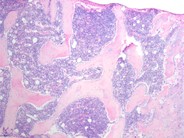

The prominent myeloid hyperplasia is best seen in this view. There are >10 rows of myeloid precursors seen in the paratrabecular area but no terminal myeloid maturation. Normally myeloid cells in this region are 1-3 cells deep.